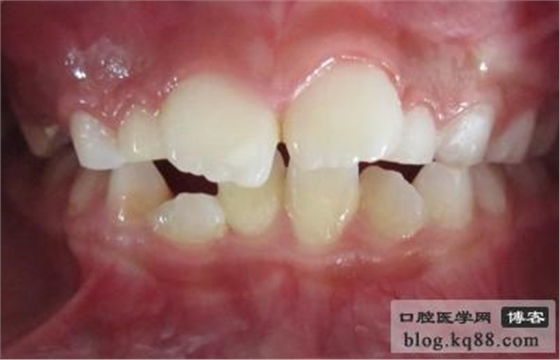

2.與替換期或與同名牙相比遲萌明顯。

3.需助萌的牙已達(dá)牙槽嵴頂部,切端在齦黏膜下,可被捫及,但因局部軟組織致密,萌出困難者。

齦瓣切除助萌術(shù)前